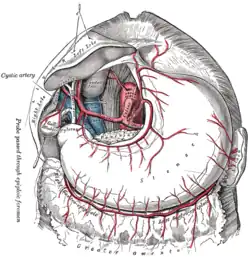

The cystic artery branches from the right hepatic artery. | |

Relationship to other vessels. (Note that relationships are highly variable -- see below.) | |

The cystic artery (also known as bachelor artery) is (usually) a branch of the right hepatic artery that provides arterial supply to the gallbladder and contributes arterial supply to the extrahepatic bile ducts.

It usually passes posterior to the common hepatic duct within the cystohepatic triangle. Within the triangle, it is usually superior to the cystic duct (if it does not pass superior to the cystic duct, it may be situated outside the triangle).[1]

Upon reaching the superior aspect of the neck of the gallbladder, it splits into superficial and deep branches. These branches then form an anastomotic network over the surface of the body and fundus of the gallbladder.[1]

- The superficial branch (or anterior branch) passes subserously over the left aspect of the gallbladder.

- The deep branch (or posterior branch) runs between the gallbladder and gallbladder fossa, terminating at the peritoneum attached to the liver surface.